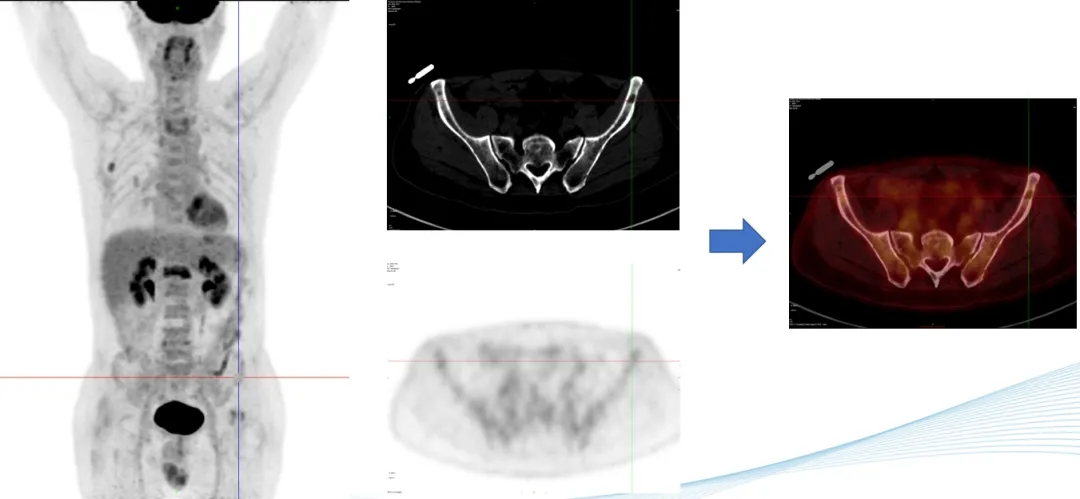

部分PET-CT影像图

前海人寿南宁医院核医学科PET-CT中心的阅片团队对扫描获得的李叔叔的全身影像图片反复多次的观察与比对,凭借着二十几年丰富的阅片经验,核医学科陈伟华主任发现,李叔叔肩胛骨、腰椎多处、双侧髂骨、左侧耻骨等出现了斑点片状、虫蚀样等形态溶骨性骨破坏,考虑恶性病变,多发性骨髓瘤可能性大,建议李叔叔立即进行骨髓穿刺检查。病理学检查结果证实了陈主任的影像诊断。腰痛的罪魁祸首终于找到,目前李叔叔已针对病因进行精准联合化疗。